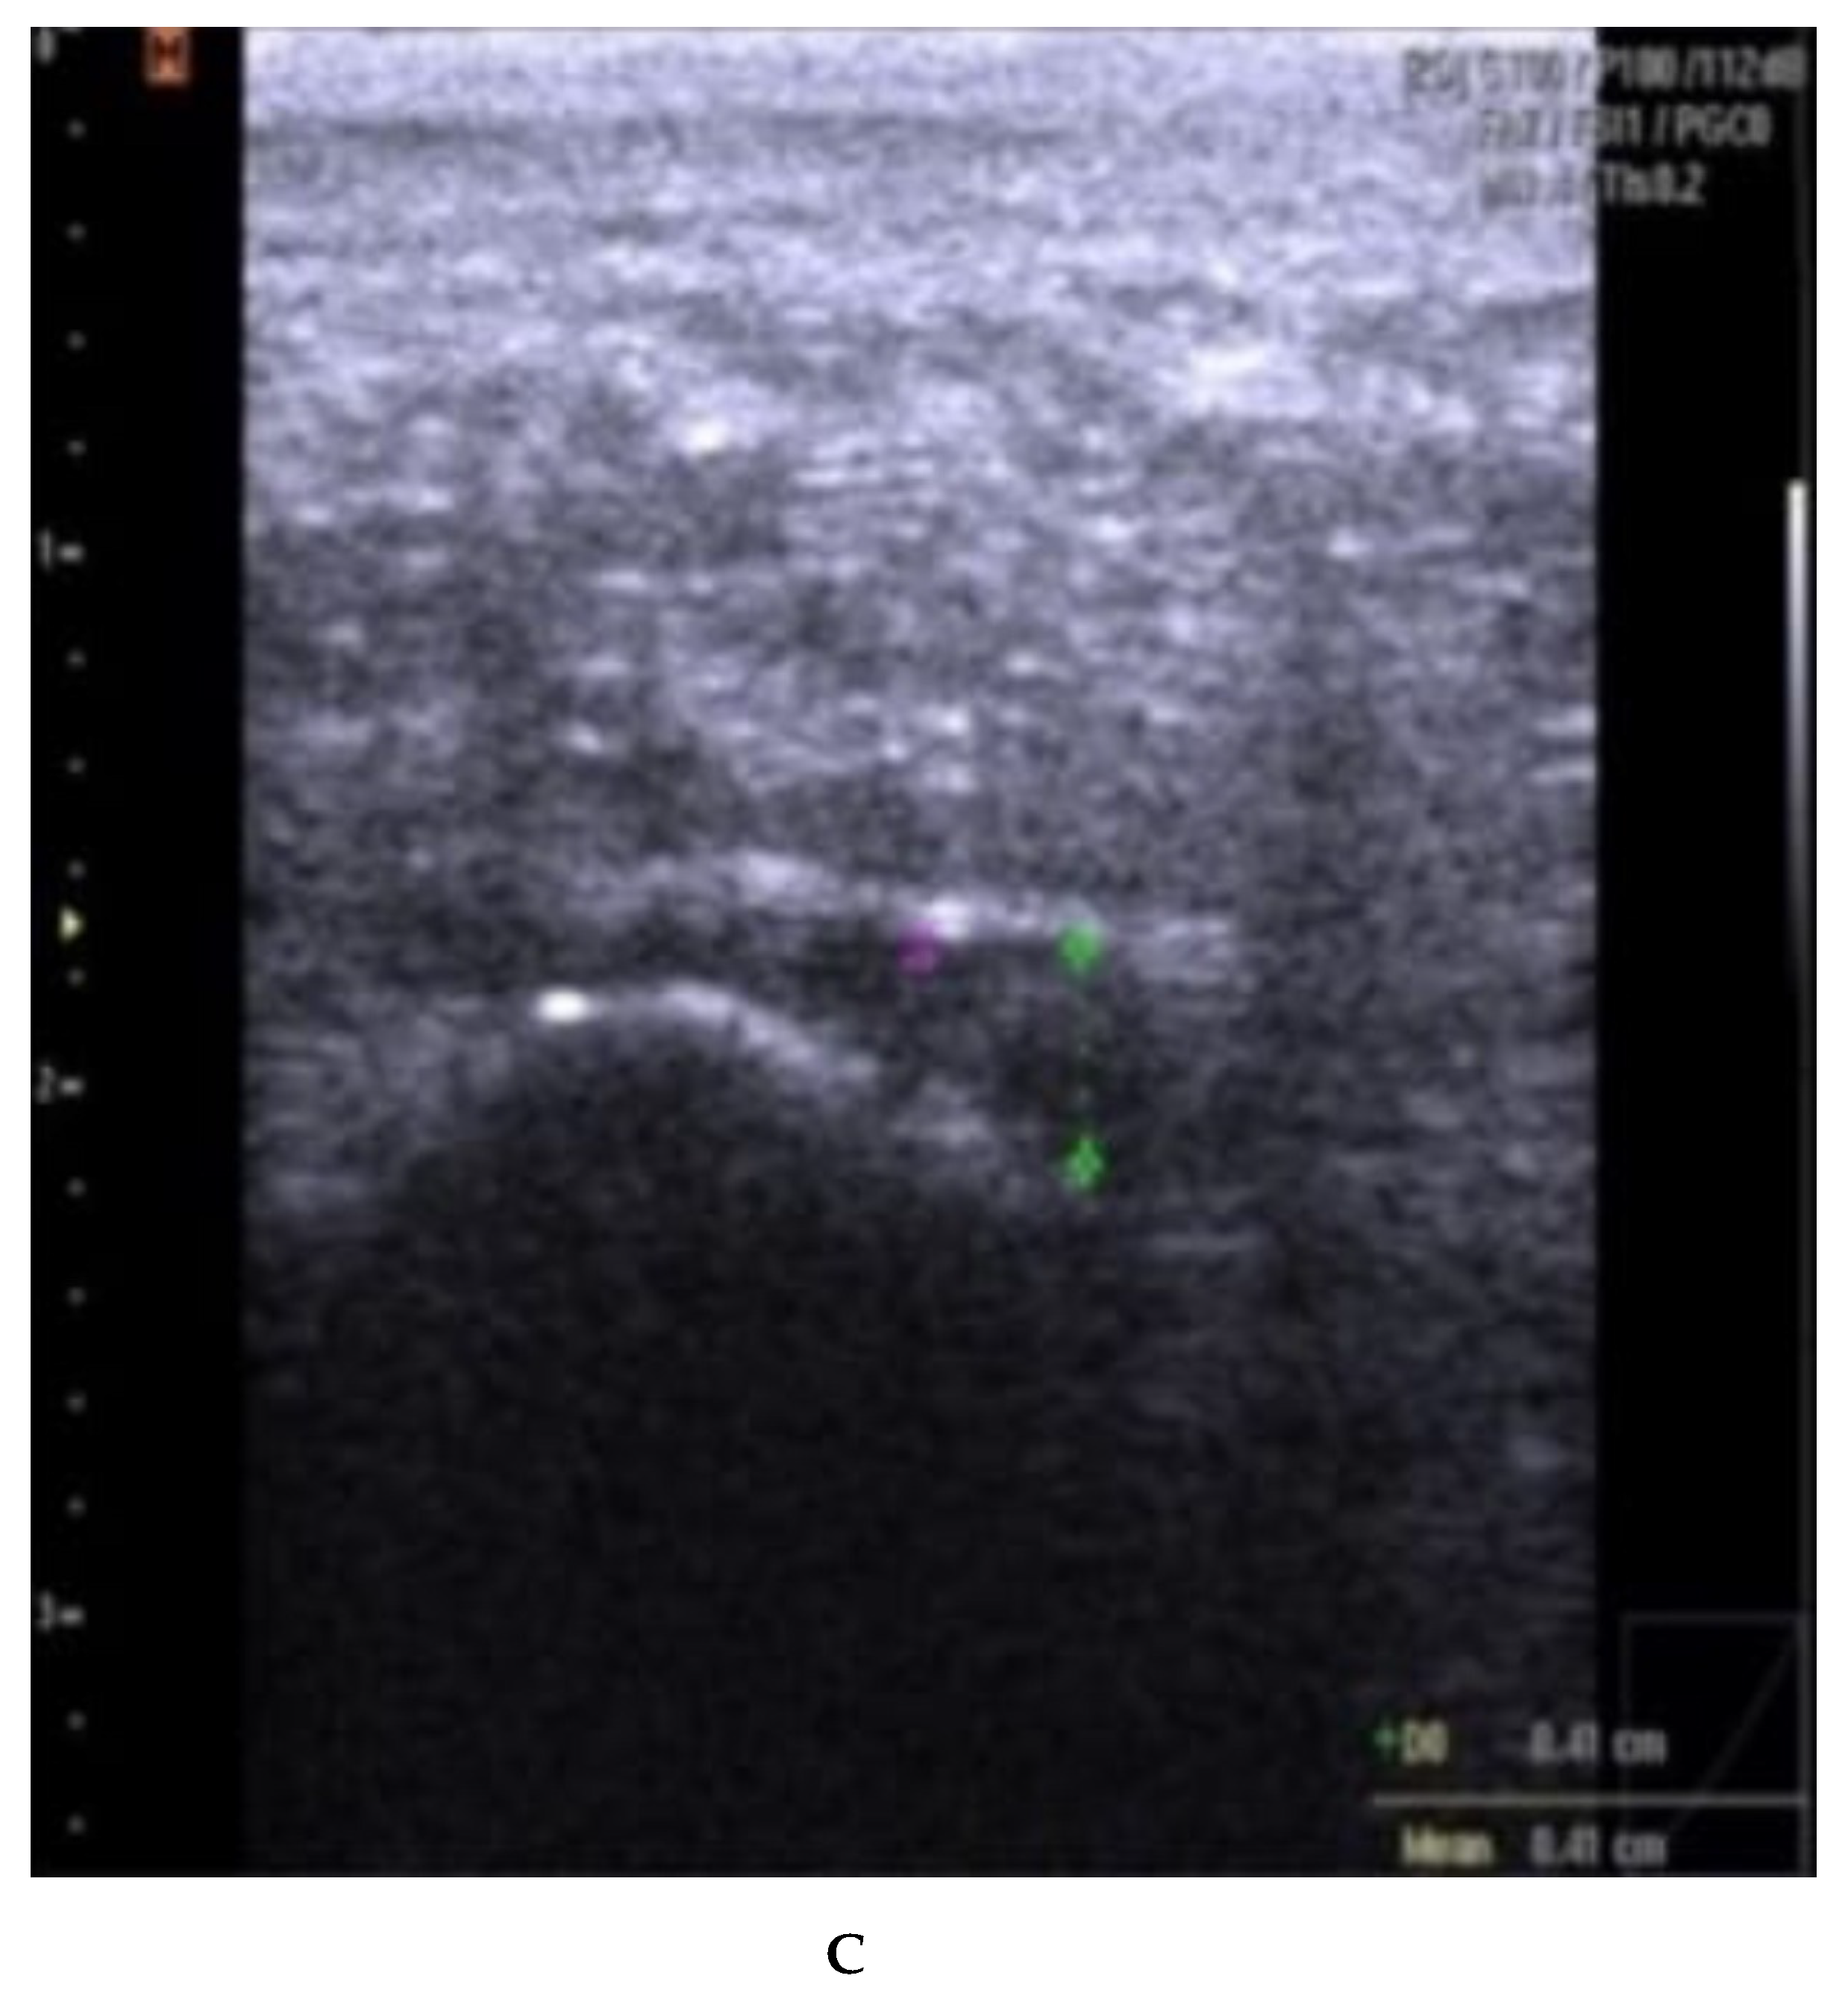

Fascia thickness and echogenicity. All patients had an increased plantar fascia thickness (3.50–8.0 mm) at baseline when measured with MSKUS, and all had hypo-echogenicity. There was a significant difference in the reduction of the plantar fascia thickness between the two groups at 4 weeks follow-up in favor of CSI + TUS (p = 0.004, Table 5), as also shown in Figure A1 and demonstrated in ultrasound images in Figure A2 and Figure A3. At the 12-week follow-up, plantar fascia thickness was significantly higher in the CSI + TUS group (p = 0.012), with an insignificant difference in the decrease between both groups (p = 0.216).

In group A (ESWT), the decrease in plantar fascia thickness correlated significantly positively with function (PFPDS) at both follow-up visits (p = 0.038 and p = 0.025) (Figure A4). The decrease in plantar fascia thickness did not correlate significantly with pain improvement at both follow-up visits (Figure A5). In group B (CSI + TUS), the decrease in plantar fascia thickness correlated positively with pain improvement at both follow-up visits (p = 0.025 and p < 0.001; Two-tailed analysis. Figure 1). The decrease in plantar fascia thickness also correlated significantly with PFPDS improvement at both follow-up visits (p = 0.015 and p < 0.001; Figure 2).

Echogenicity change (Figure A2 and Figure A3) from hypoechoic to iso- or hyperechoic was statistically significant in both groups at 12-week follow-up, but no significant difference was found between the groups (p = 0.208; Table A1).

(A–C): plantar fascia thickness and echogenicity before, after 4 weeks, and 12 weeks follow-up (CSI followed by therapeutic US). (A). Plantar fascia thickness (0.55 cm) and echogenicity (hypoechoic) before CSI injection followed by therapeutic US; Ankles in 90° dorsiflexion; Images obtained just medial to the midline, at the proximal end of the plantar fascia, distal to its origin, from the medial tubercle of the calcaneus; Thickness of the plantar fascia was measured from the base of the medial calcaneal tubercle, where a bright echogenic line was easily visible. (B). Plantar fascia thickness (0.44 cm) and echogenicity (hypoechoic) after 4 weeks. (C). Plantar fascia thickness (0.41 cm) and echogenicity (hypoechoic) after 12 weeks.